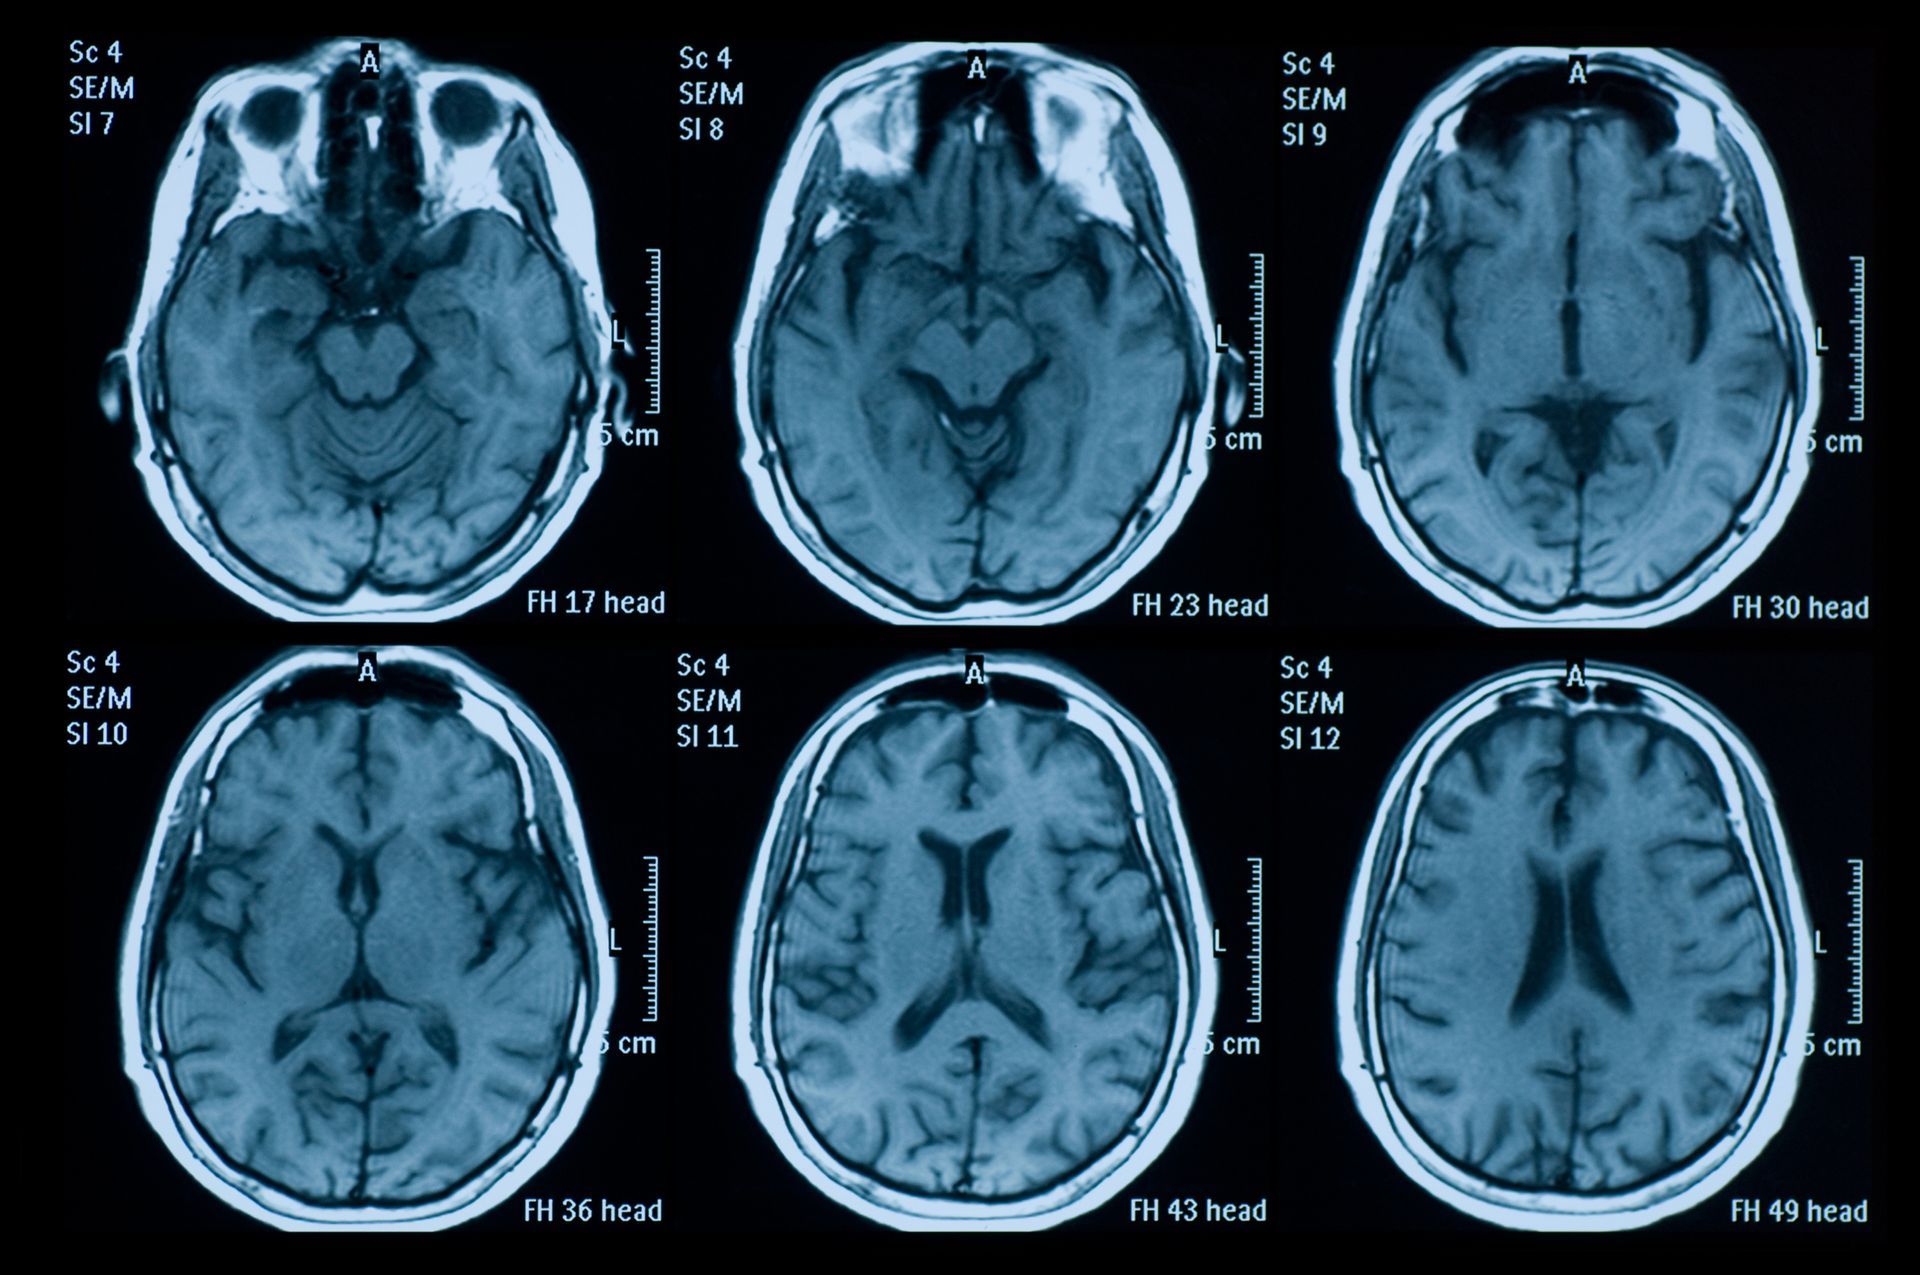

We offer applications training of MRI and CT systems to technologist. We use experienced registered trainers. In a training session, we accomplish protocol implementation, image optimization and technologist familiarization with the imaging scanner. Our goal is to create a positive experience where the technologist is able to effectively operate the system to create diagnostic images.